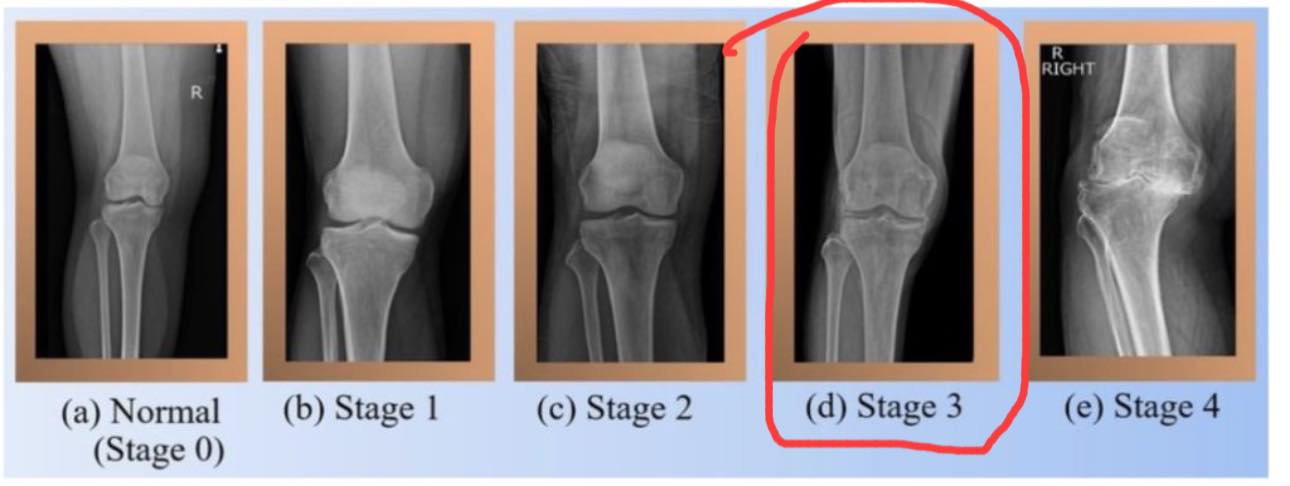

72歲的龍阿姨,住在新竹縣竹東鎮,長期受到第三期膝蓋退化性關節炎的困擾。這是一種以關節軟骨退化為主的慢性疾病,隨著年齡增長及關節過度使用,膝蓋逐漸出現疼痛、僵硬和行動不便等症狀。對於龍阿姨來說,這樣的病痛已經讓她的生活陷入困境,每次出門散步都成了一項挑戰,走路僅僅三到五分鐘,膝蓋就會開始劇痛。上下樓梯更是難上加難,每一步都需要扶著樓梯倒退慢慢下來,僅僅幾階樓梯就耗費了她極大的精力。

退化性膝關節炎的主要原因是關節軟骨長期磨損,加上滑液減少導致的關節內摩擦加劇,最終引發炎症和疼痛。像龍阿姨這樣的患者,往往因長時間的膝蓋過度使用或不正確的姿勢累積了問題。此外,肥胖、遺傳因素以及長期勞動也都是可能的誘因。然而,這種疾病早期症狀較輕,許多患者忽略了及早干預,導致症狀加重,最終進展到需要手術的地步。